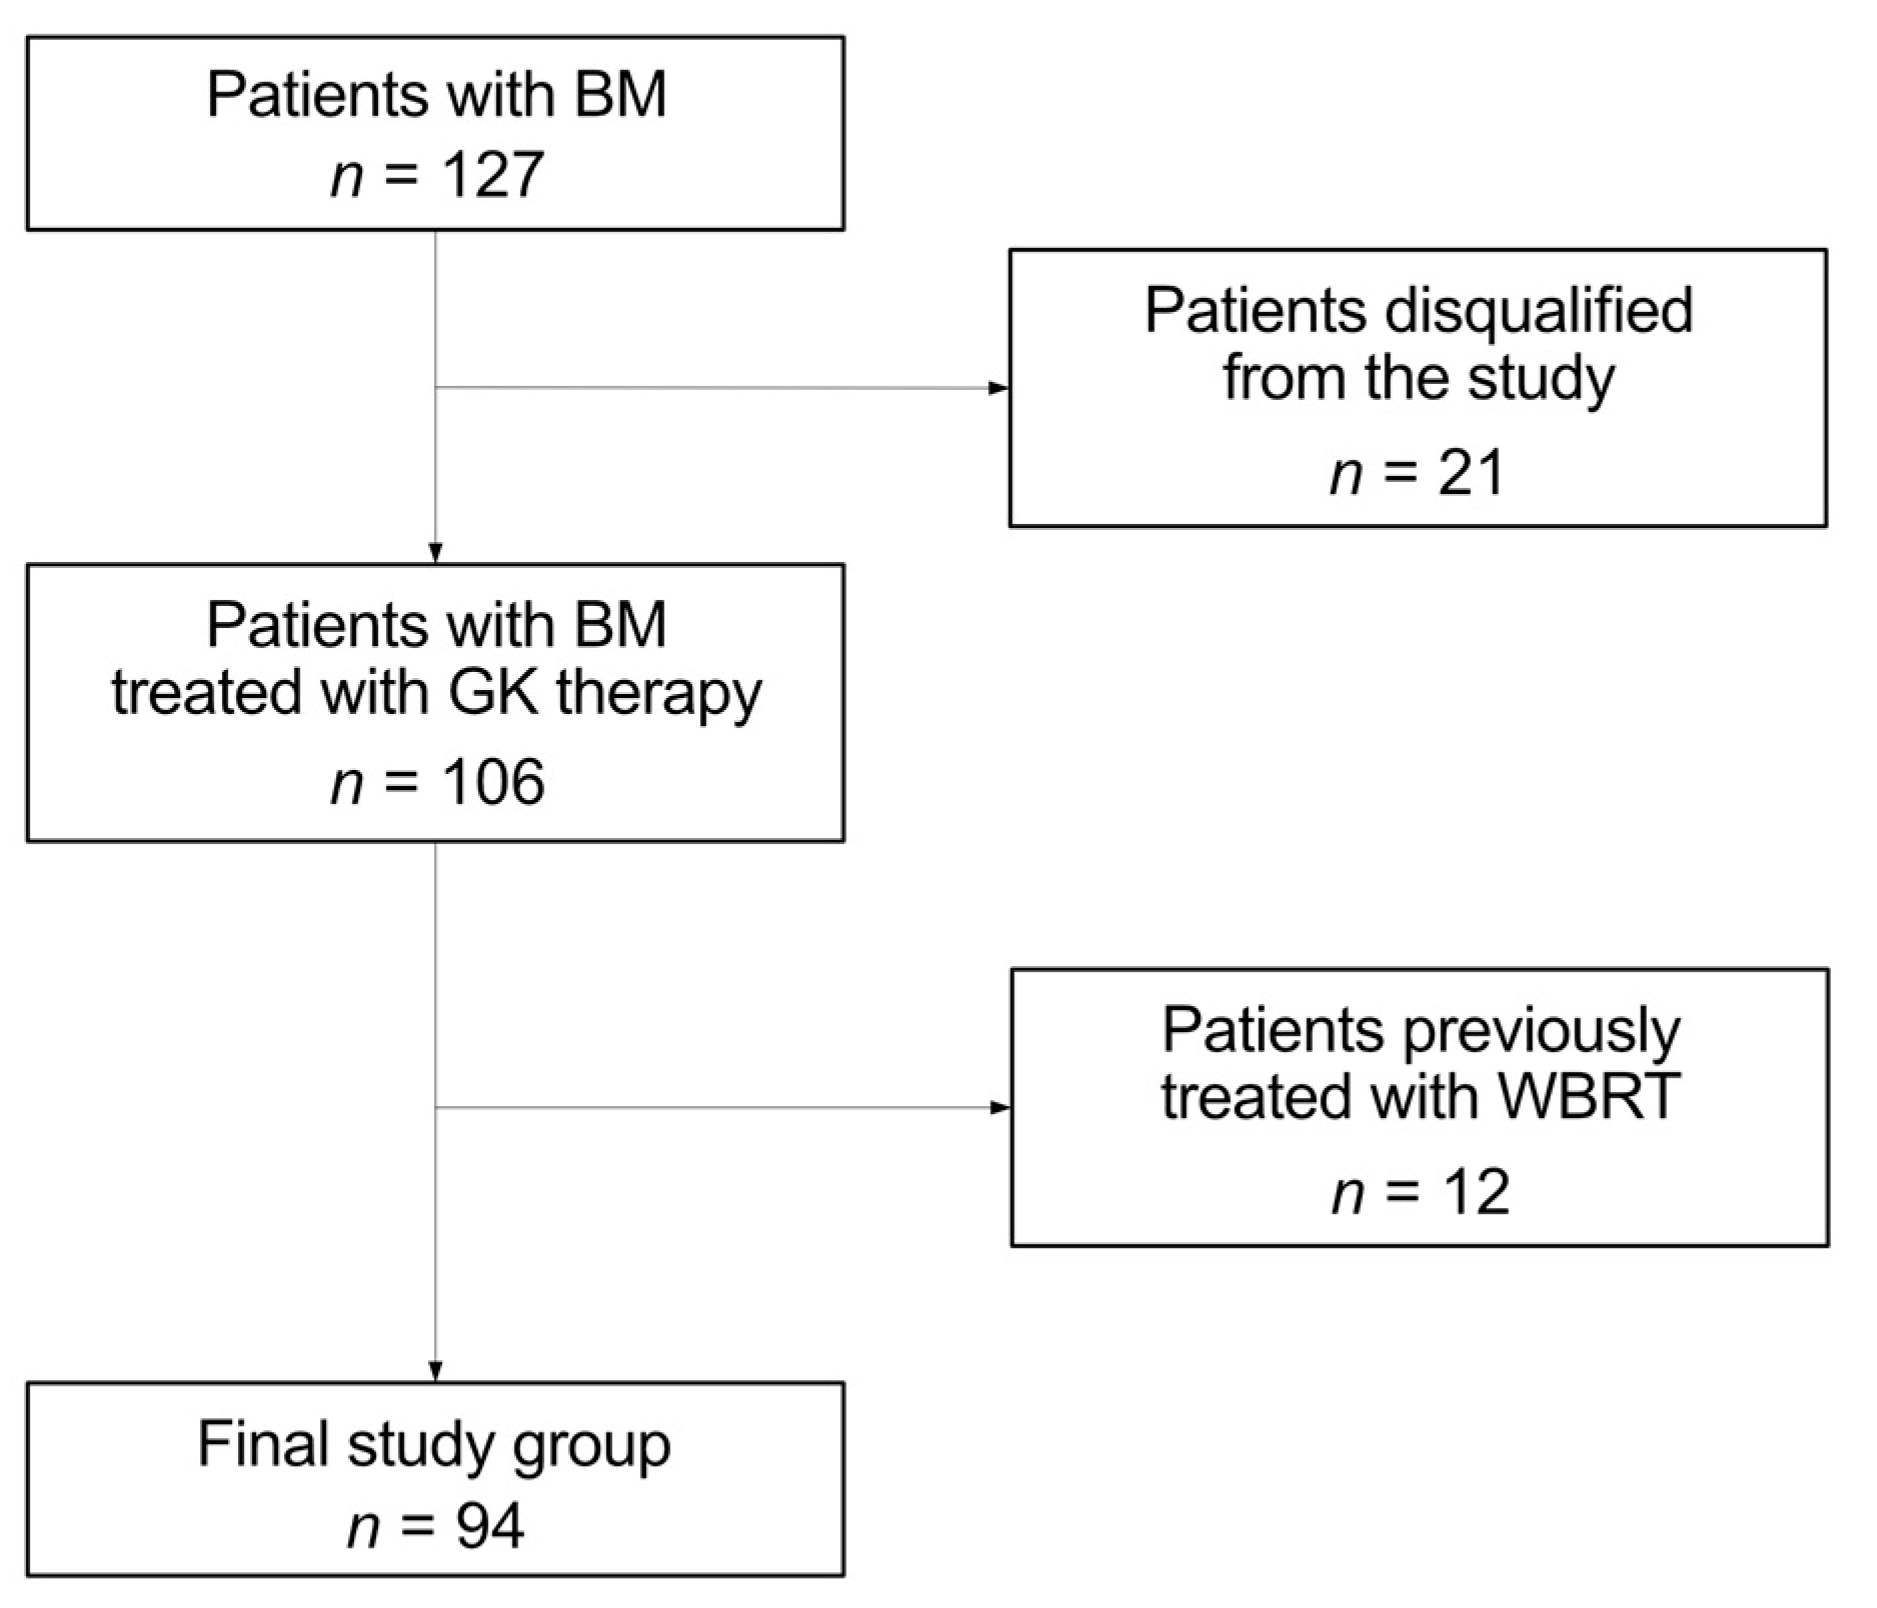

2.1. Patient Selection, Inclusion and Exclusion Criteria